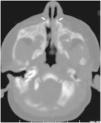

Durante el segundo ingreso se le realizó una TC de las fosas nasales en la que se observó la disminución de la distancia entre ambos procesos nasales del maxilar (fig. 1), incisivo central único congénito (fig. 2a y b) y paladar triangular (fig. 3) con cresta central (fig. 4), hallazgos compatibles con ECOP.

La paciente que aquí se presenta cumplía con estos hallazgos descritos. Asimismo, presentaba una pequeña cresta ósea en la línea media por debajo del paladar duro en la reconstrucción coronal (fig. 4) y un gran diente incisivo único central (fig. 2). Éstas son alteraciones típicamente asociadas a la ECOP; es particularmente destacable la alteración de la dentición, ya que el megaincisivo central único puede ser una manifestación de la holoprosencefalia, por lo que se indica un estudio de imagen cerebral, preferiblemente una resonancia magnética (RM)1,4,6. En el presente caso se realizó ecografía y RM cerebral, que no mostraron alteraciones.